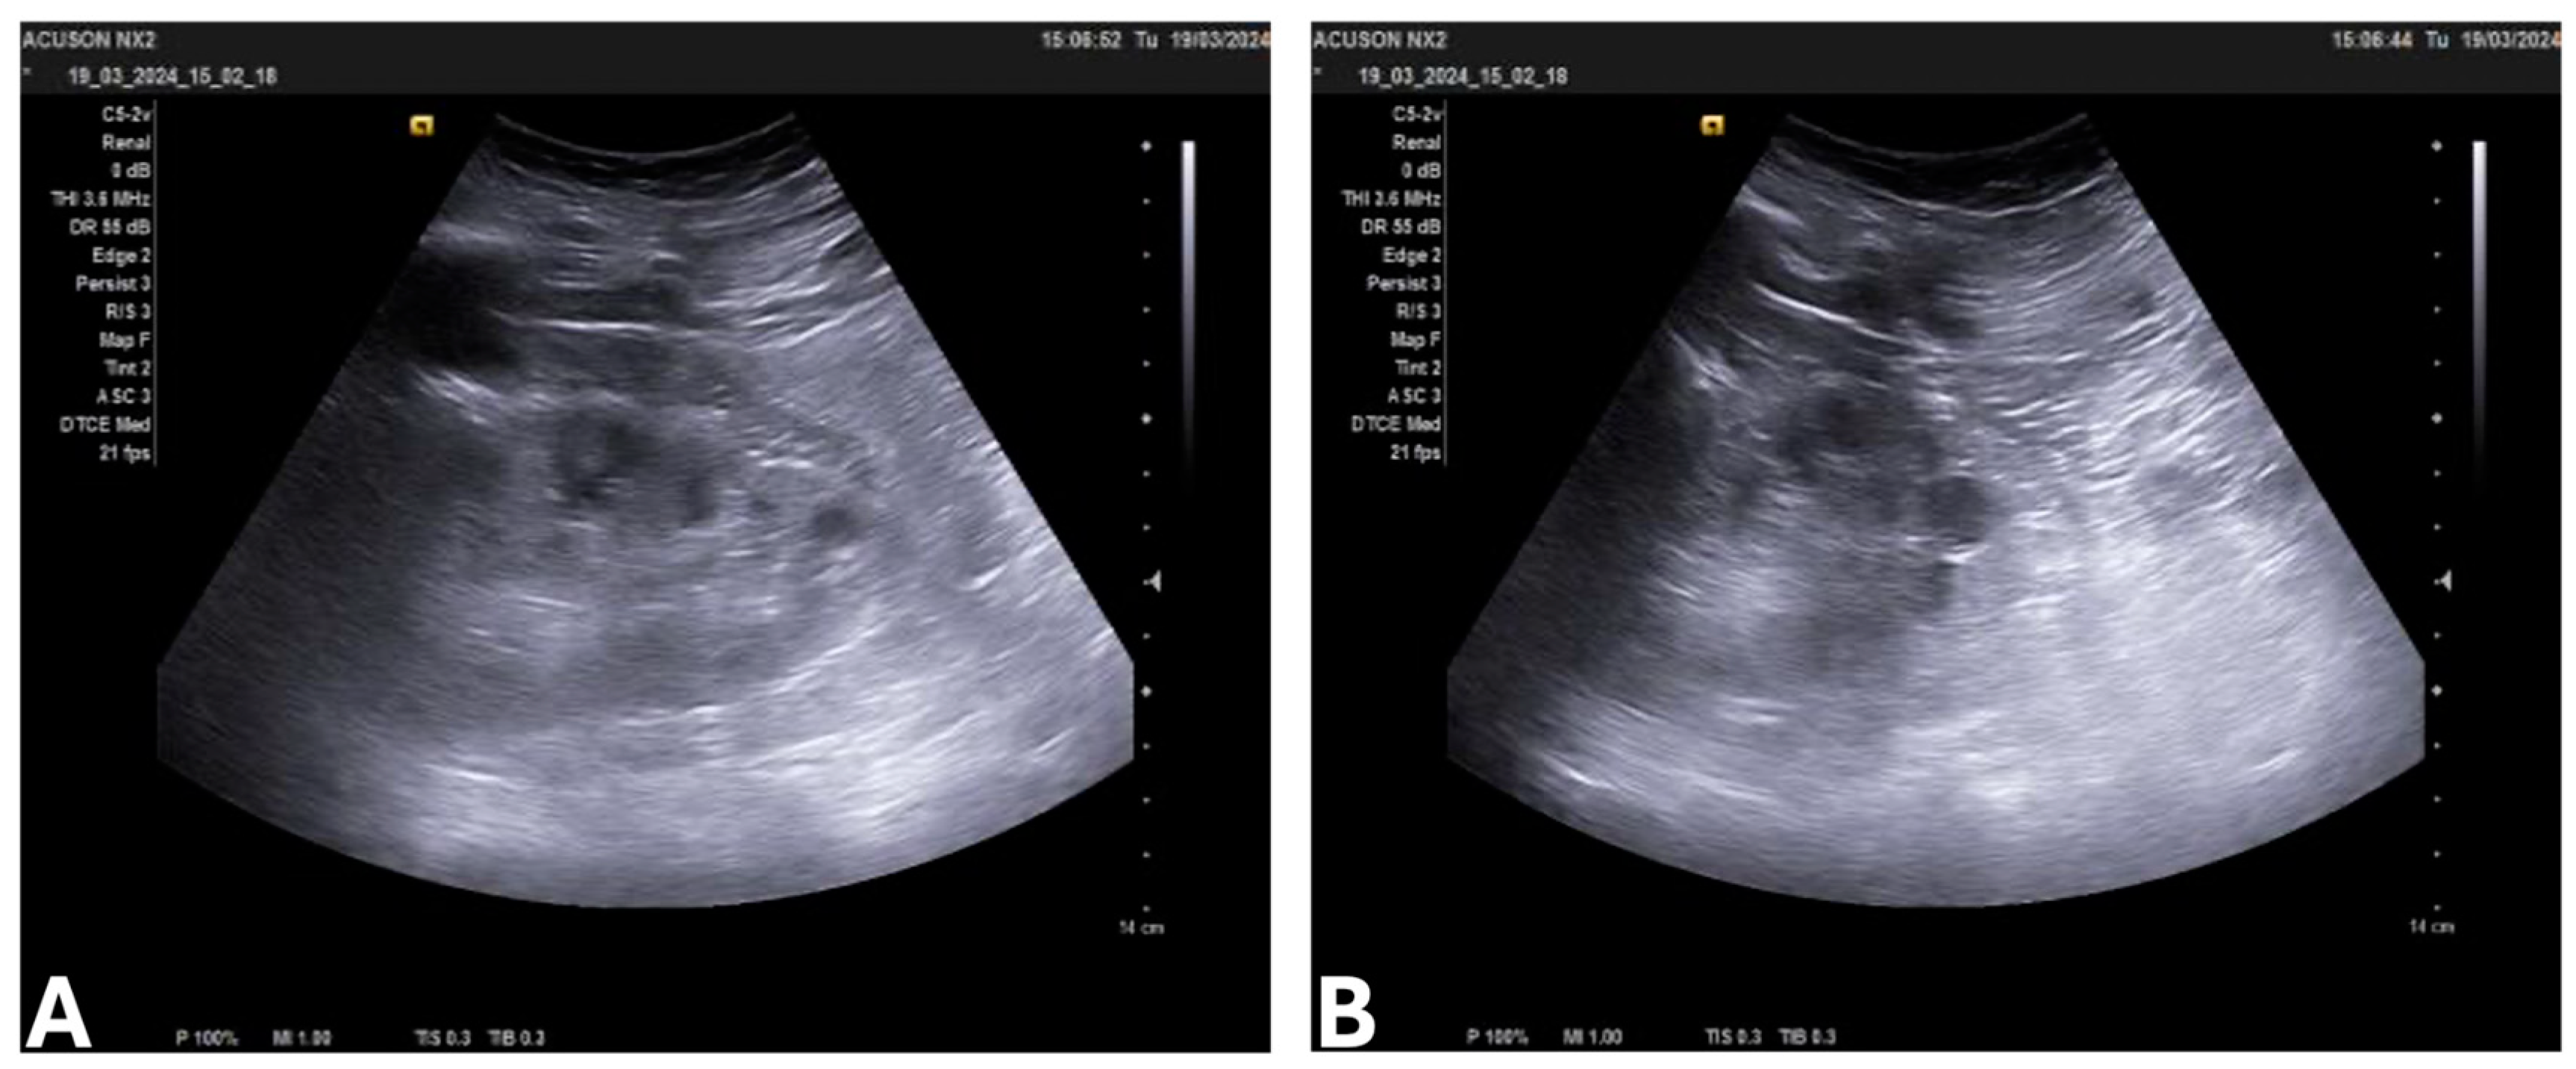

3.4. Laboratory Findings, Imaging, and Stage of ADPKD